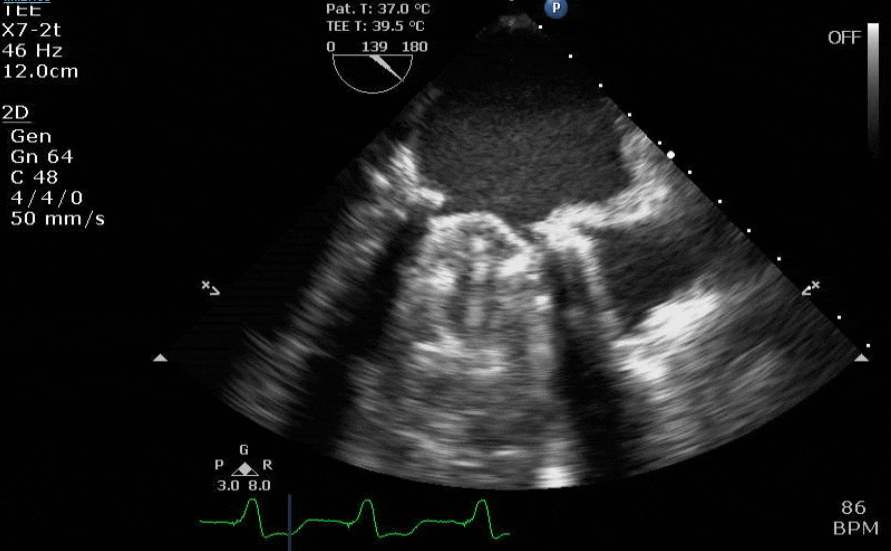

S/p MI. Clearly something bad happening. What is somewhat unique about this pathology (hint: the transgastric 2-chamber is most helpful for this question)?

Cool. Typically you think of just a chordal rupture with post MI MR, but a whole chunk of pap muscle tore off and is flopping in the wind here. Presumably post medial given single blood supply going to that pap muscle from RCA.

I see the defect in the inferior wall that @pocafx is referring to in the 2 chamber view (which further speaks to RCA infarct/post-med pap rupture), but I’m not seeing enough to call it as a VSD on that view alone. Though I am looking at it on a cell phone. I’d want to interrogate further before I could definitively call it for my surgeon.

Also, at risk of sounding pedantic, it’s technically flail, not prolapse.

If you look at the 3d it really looks like the flail segments are lateral in the A1/A2 region. Same goes for the ME 5 chamber which should be picking up A1. Lends credence to not being a PM pap rupture, although that would be irregular given the blood supply...

Yea, you’re right, flail segment appears to be more AL. I think I saw MI/ruptured pap and got tunnel vision. Would have to be either atypical solo blood supply to the AL pap or it has an accessory pap with solo blood supply and that’s what infarcted/ruptured. It’s unlikely the patient would be alive long enough after the left main went down for that to be the reason for AL pap rupture.

It is indeed the anterolateral papillary muscle that's ruptured. PM is 8-12 x more common from what I have read, so it was a reasonable initial thought anyway.

This guy spent a week in the ICU with a balloon pump in place prior to OR. He was exceptionally unwell.

He underwent CABG + MVR with a bioprosthetic valve. Pictures to follow. Last I saw, he got a trach and was still in the ICU.